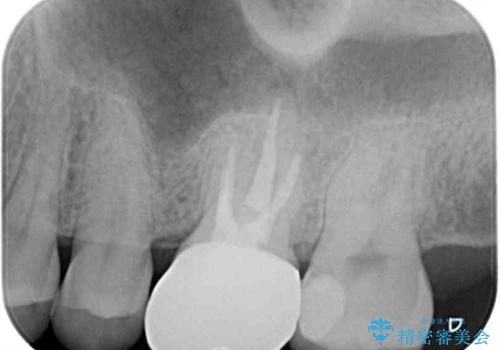

- 鼻づまりがひどく耳鼻科を受診したところ、虫歯が原因の可能性があるとのことで来院された患者様です。

レントゲン写真では根尖部に病変があるように見えたため、神経が失活しているのかチェックをしたところ、生活反応はありませんでした。

根管治療を行い、症状の経過を見て、セラミッククラウンにて補綴治療を行うこととしました。

レントゲン的には根管治療の治癒経過良好で、手術後に症状や違和感がなくなり、無事セラミッククラウンを装着することができました。